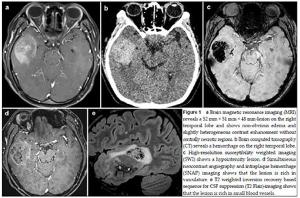

20170512093522 Figure 1 a Brain magnetic resonance imaging (MRI) reveals a 52 mm × 51 mm × 48 mm-lesion on the right temporal lobe and shows non-obvious edema and slightly heterogeneous contrast enhancement without centrally necrotic regions.b Brain computed tomography (CT) reveals a hemorrhage on the right temporal lobe. c High-resolution susceptibility weighted imaging (SWI) shows a hypointensity lesion.d Simultaneous noncontrast angiography and intraplaque hemorrhage (SNAP) imaging shows that the lesion is rich in vasculature.e T2 weighted inversion recovery based sequence for CSF suppression (T2 Flair)-imaging shows that the lesion is rich in small blood vessels.